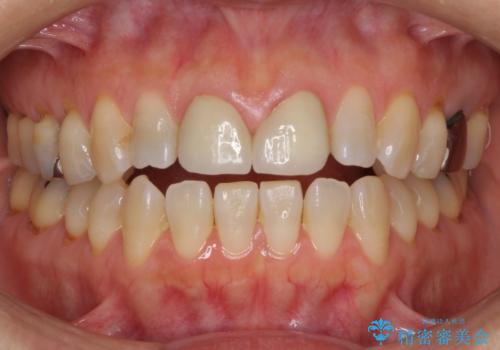

前歯のすきっぱ&奥歯の虫歯 セラミッククラウンで徹底的に治す

- 前歯のすきっぱを主訴にご来院された患者様です。他院でつめものやラミネートべニア(前歯の表面のみセラミックを貼り付ける)を行っていましたが、頻繁に外れることに悩まれており、クラウン(歯全体をセラミックがつつむ)をご希望されました。また、奥歯に大きな虫歯があり、歯が割れていたため、奥歯の治療も併せて行いました。

今回はまず欠けた場所を修復して見た目を回復させたのち、ラミネートべニアの仮歯をつくり、しばらく使用して考えて頂きました。メリットやデメリットを説明した結果、外れにくいセラミッククラウンをご選択頂きました。

咬み合わせや元のご自身の歯の色に特徴があったため、セラミッククラウンを修正したり、隣の歯を金属を外して白いつめものに変えたりして経過観察を長めに行いました。

患者様には大変満足して頂きました。